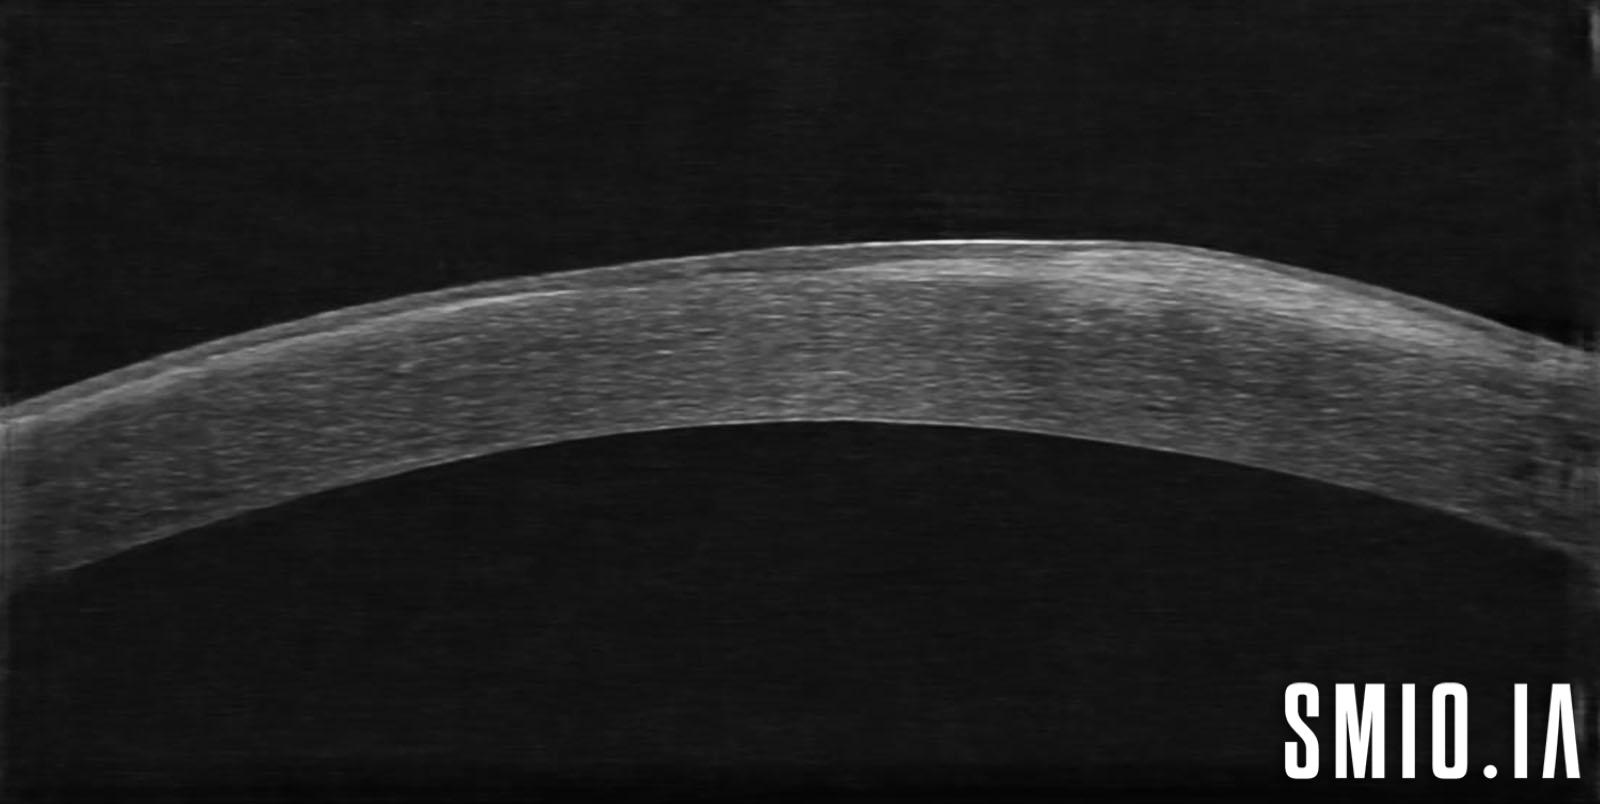

Description: La dégénérescence nodulaire de Salzmann chez une femme de 76 ans qui consulte pour la sécheresse oculaire et acuité visuelle basse, elle a également des cicatrices sous-épithéliales associées, la dégénérescence nodulaire de Salzmann est une condition lentement progressive dans laquelle des nodules gris-blanc bleuâtres mesurant 1 à 3 mm sont vus à La cornée à la couche de Bowman, généralement bilatéral. Ces nodules élevés peuvent être situés près du limbe ou dans la cornée à la mi-périphérie

Appareil d'imagerie: Huvitz HIS-5000U-Canon80D Optol Revo SOCT Copernicus